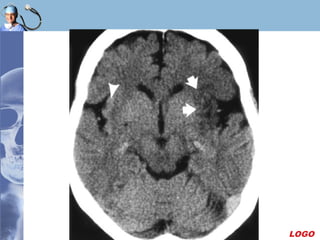

Trong 24h đầu, độ nhạy chỉ khoảng 50%

LOGO

105 phút sau tai biến105 phút sau tai biến